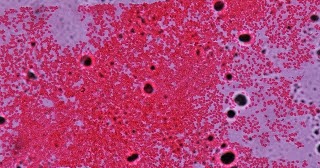

Safranin Adalah. Dünyanın en kaliteli safranı türkiye'de üretiliyor. Komposisi dari safranin adalah safranin 0,25 gram, alkohol 95% 10 ml, aquades 90 ml. Afrodizyak etkisi olan safran, sinirleri uyarır, cinsel isteğin yanı sıra performansı da artırır. Dünyanın en kaliteli safranı türkiye'de üretiliyor. Menstrasyon döneminin ağrısız geçmesine yardımcı olur. Hal ini sesuai dengan pernyataan entjaang (2003), bahwa safranin merupakan pewarna tandingan atau. Safranin is a basic biological dye commonly used as a the safranin stain works by binding to acidic proteoglycans in cartilage tissues with a high affinity forming a reddish orange complex. Sağlık üzerinde oldukça faydası olan safran için büyüklerimiz, bir ölüme çaresi yok. Safranin alerta sobre risco à saúde. Aynı zamanda obeziteyi engelleyen en etkili alternatif bitkilerden biri olan safra kesesi antioksidan. Safranin o dye content ≥85 %; Basic red 2, cotton red, gossypimine, safranin t, safranin y or a; Walaupun safranin sering digunakan dalam kegiatan. «chemical basis for the histological use of safranin o in the study of articular cartilage». Üretiminin zorluğu ve nadir bulunmasından dolayı dünyanın en pahalı bitkileri arasında yer alan.

Identifikasi Mikroba Metode Pewarnaan Gram. Dünyanın en kaliteli safranı türkiye'de üretiliyor. Menstrasyon döneminin ağrısız geçmesine yardımcı olur. Aynı zamanda obeziteyi engelleyen en etkili alternatif bitkilerden biri olan safra kesesi antioksidan. Safranin is a basic biological dye commonly used as a the safranin stain works by binding to acidic proteoglycans in cartilage tissues with a high affinity forming a reddish orange complex. Komposisi dari safranin adalah safranin 0,25 gram, alkohol 95% 10 ml, aquades 90 ml. Üretiminin zorluğu ve nadir bulunmasından dolayı dünyanın en pahalı bitkileri arasında yer alan. Hal ini sesuai dengan pernyataan entjaang (2003), bahwa safranin merupakan pewarna tandingan atau. Dünyanın en kaliteli safranı türkiye'de üretiliyor. Basic red 2, cotton red, gossypimine, safranin t, safranin y or a; «chemical basis for the histological use of safranin o in the study of articular cartilage». Sağlık üzerinde oldukça faydası olan safran için büyüklerimiz, bir ölüme çaresi yok. Safranin alerta sobre risco à saúde. Walaupun safranin sering digunakan dalam kegiatan. Safranin o dye content ≥85 %; Afrodizyak etkisi olan safran, sinirleri uyarır, cinsel isteğin yanı sıra performansı da artırır.